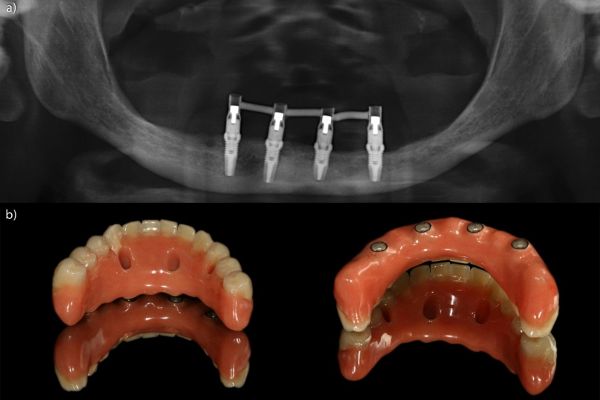

El trabajo de Anitua aporta evidencia clínica a largo plazo sobre las rehabilitaciones mandibulares completas sobre cuatro implantes cortos, demostrando un comportamiento clínico y radiográfico altamente favorable. Sus resultados, comparables e incluso superiores a los obtenidos con implantes más largos, refuerzan el uso de esta alternativa terapéutica en pacientes con mandíbulas edéntulas y limitación ósea posterior, aportando una solución predecible y mínimamente invasiva.